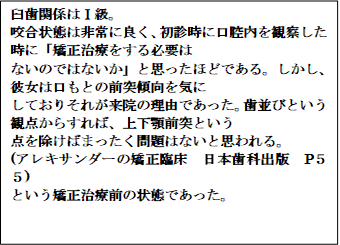

前回は左の写真(上顎前突)を説明しました。今回は右の写真を説明していきたいと思います。

歯・口腔の健康診断パネル③ 抜粋 アレクサンダーの矯正臨床p55抜粋

20世紀の最高峰の矯正医アレクサンダー先生が完全な個性正常咬合であると認めている

歯並びに対して口もとが前突気味だと言うだけで患者さんの主訴(同意)もかえりみず抜歯をすることが頭に浮かんでしまう矯正医が少なからずいます。

今回の症例は患者さんの強い主訴があるためにアレクサンダー先生は抜歯矯正処置を行いました。

歯・口腔の健康診断パネル③ 抜粋 アレクサンダーの矯正臨床p55抜粋